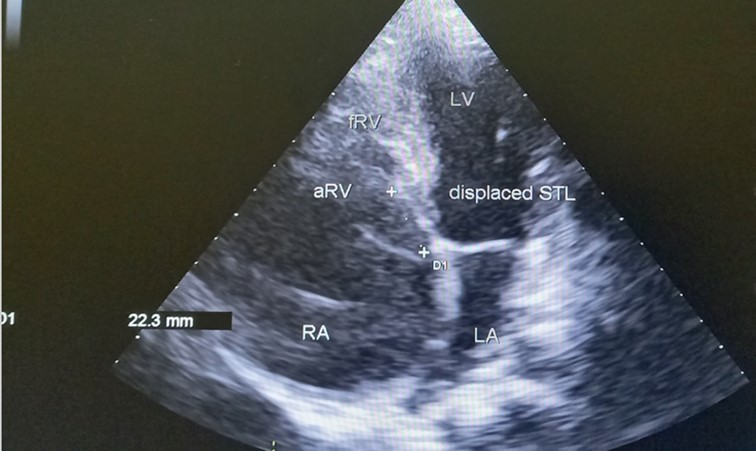

The patient underwent echocardiography (Figure 3 ) showing a low insertion of the septal and posterior leaflets of the tricuspid valve 22 mm below the tricuspid annulus, the anterior leaflet having reduced reduced mobility. Significant dilatation of the the right atrium by atrialisation of the right ventricle (RV). The rudimentary RV and its atrial stump are dilated and responsible for compression of the LV. There was no tricuspid insufficiency. No other associated congenital anomaly. However, we found a large floating thrombus in the right atrium measuring 64 mm x 30 mm in diameter. This was therefore Ebstein's disease at stage C of the Carpentier classification. The apical displacement of the tricuspid septal valve was 22 mm or 15 mm/m2). The surface area of the atrium and the atrialized right ventricle was 45 cm2 , the surface area of the right ventricle and the left cavities was 30 cm2 , the Celermajer index was calculated at 1.4 ( Grade 3).

Figure 3.Transthoracic echocardiography, apical four chambers view . Apical displacement of the tricuspid valve (a) and right atrial thrombus (b).